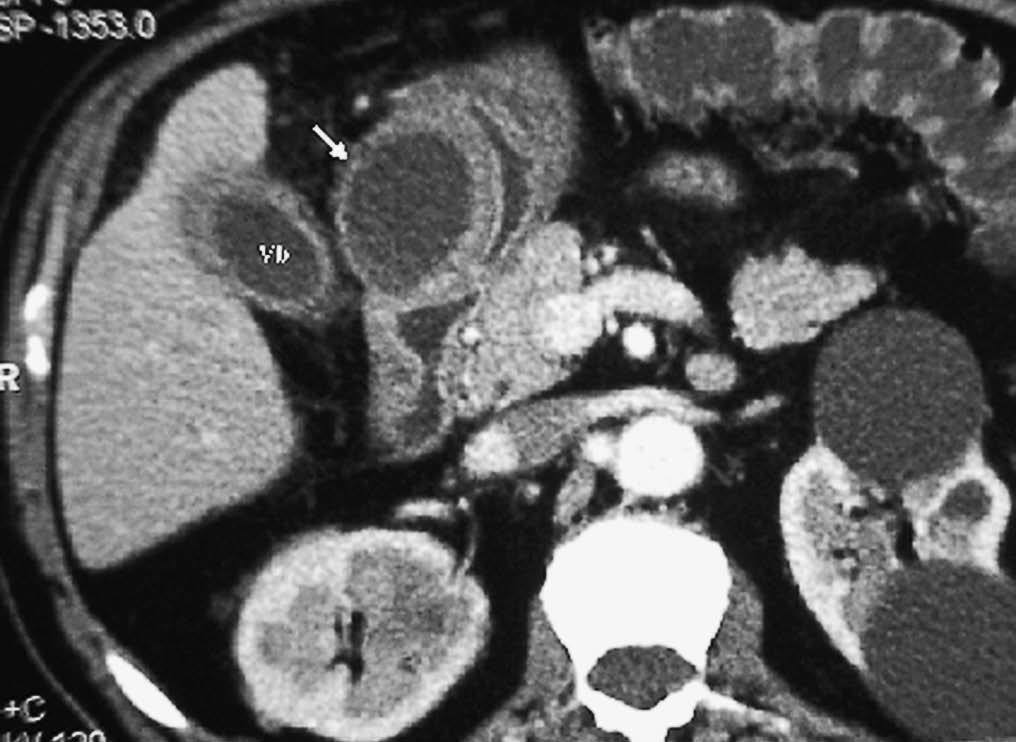

La colecistitis también puede afectar al duodeno, produciendo un engrosamiento de pared secundario a la extensión de la inflamación vesicular. Dicha inflamación puede provocar un absceso de pared duodenal (fig. 13). La existencia de un nivel hidroaéreo en la TC sugiere que se ha producido una comunicación con la luz intestinal. La inflamación puede progresar y perforar la pared duodenal ocasionando una fístula bilioduodenal, identificándose en la ecografía como un trayecto hipoecoico con paso de contenido ecogénico (gas) entre vesícula y duodeno. También se puede observar la presencia de aire en vesícula, que puede extenderse al resto de la vía biliar (neumobilia) (fig. 14). La salida de la colelitiasis a través de la fístula y su impactación en el tracto intestinal puede producir un íleo biliar20.

Fig. 13--Absceso en pared duodenal secundario a colecistitis. Tomografía computarizada con contraste intravenoso. Colección hipodensa (flecha) en contacto con la pared de la segunda porción duodenal, en proximidad a una vesícula con las paredes engrosadas (Vb).